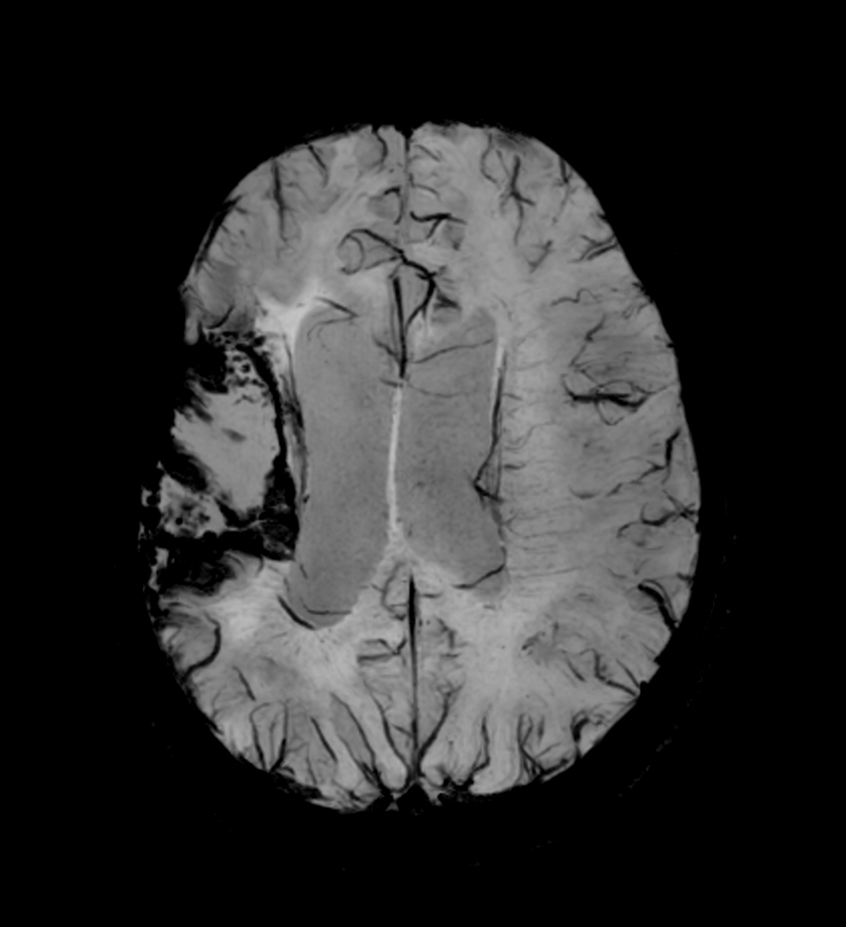

Brain glioblastoma, post-operative

Patient who was operated on glioblastoma

Axial SWIp